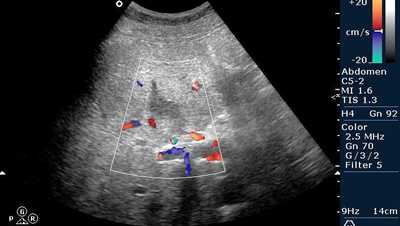

о При цветовой допплерографии может определяться гиперваскуляризация воспаленной окружающей паренхимы печени

о Для подтверждения сосудистых изменений используйте цветовую допплерографию